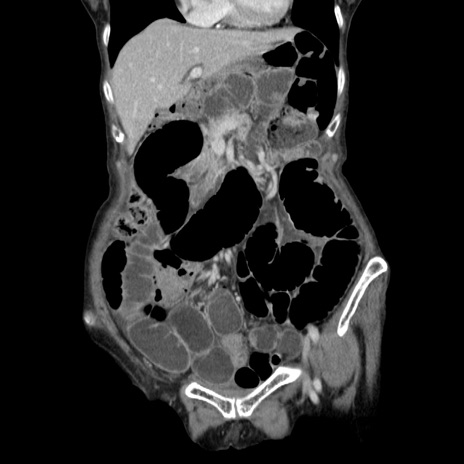

横断像

【症例】80歳代女性

【現病歴】約9時間前に食後から胸のつかえた感じあり、嘔吐あり、来院。

【既往歴】胃癌(全摘)、胆摘、虫垂炎